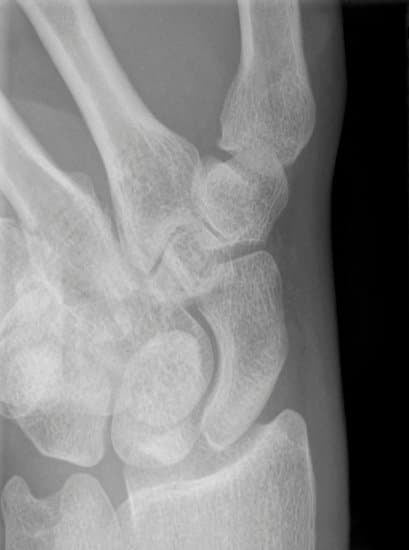

X-ray 검사

주상골 골절 여부를 확인하기 위한 1차 검사입니다.

그러나 초기 골절이 잘 보이지 않을 수 있습니다.